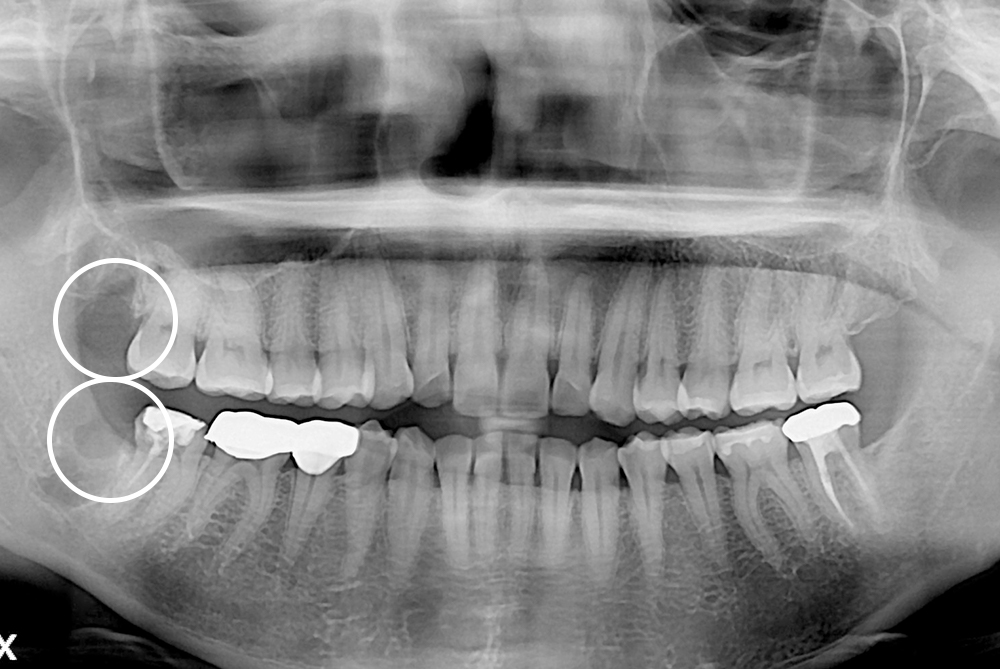

[사랑니] 매복 사랑니 발치

치료후 : 2019-03-01

세종치과는 구강악안면외과학 박사이신 원장님이 발치하는 치과입니다.